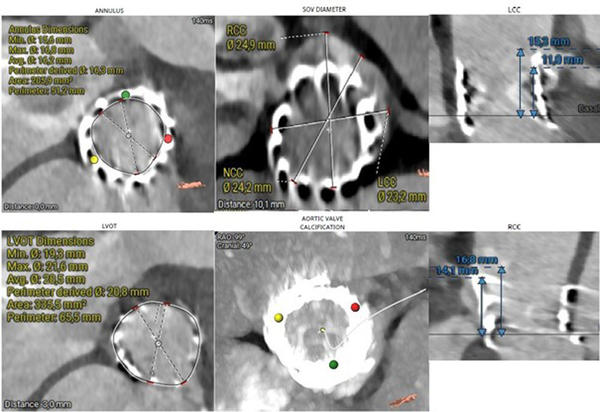

Computed tomography (CT) provides essential anatomical information. Imaging reveals that the outflow edge of the bioprosthetic stent frame extends beyond the sinotubular junction, resulting in complete coverage of the right coronary artery (RCA) ostium, which measures 11 mm in height. The left coronary artery ostium is located at a height of 14 mm, and the aortic annular height is also 14 mm. These anatomical features indicate a substantial risk of coronary obstruction in the setting of valve-in-valve (ViV) transcatheter aortic valve replacement (TAVR) (Figure 2).

Figure 2. MSCT Valve Measurements Using the 3mensio Program:

(A) Measurement of the inflow frame area of the 20 mm Sapien 3 TAVR valve. (B) and (C) 3D visualization of the Virtual Valve in a valve-in-valve configuration and assessment of the height of the right coronary artery.

Following a multidisciplinary Heart Team discussion, the patient—given her advanced age, frailty, EuroSCORE, and previous transapical TAVI—was deemed suitable for redo TAVI. Significant LVOT calcification and a small LVOT diameter precluded the use of a balloon-expandable valve. A self-expanding intra-annular prosthesis was not considered due to limited institutional experience. The use of a self-expanding supra-annular valve was associated with a high risk of left coronary artery obstruction. After careful evaluation of the anatomical and procedural risks (Figure 4), transfemoral TAVI was performed using a 23-mm self-expanding supra-annular prosthesis (Medtronic Evolut FX+) with a chimney technique to protect coronary flow.